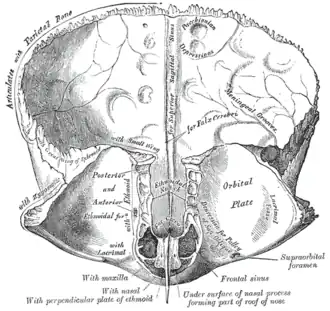

Left parietal bone. Inner surface. -

Frontal bone. Inner surface. -